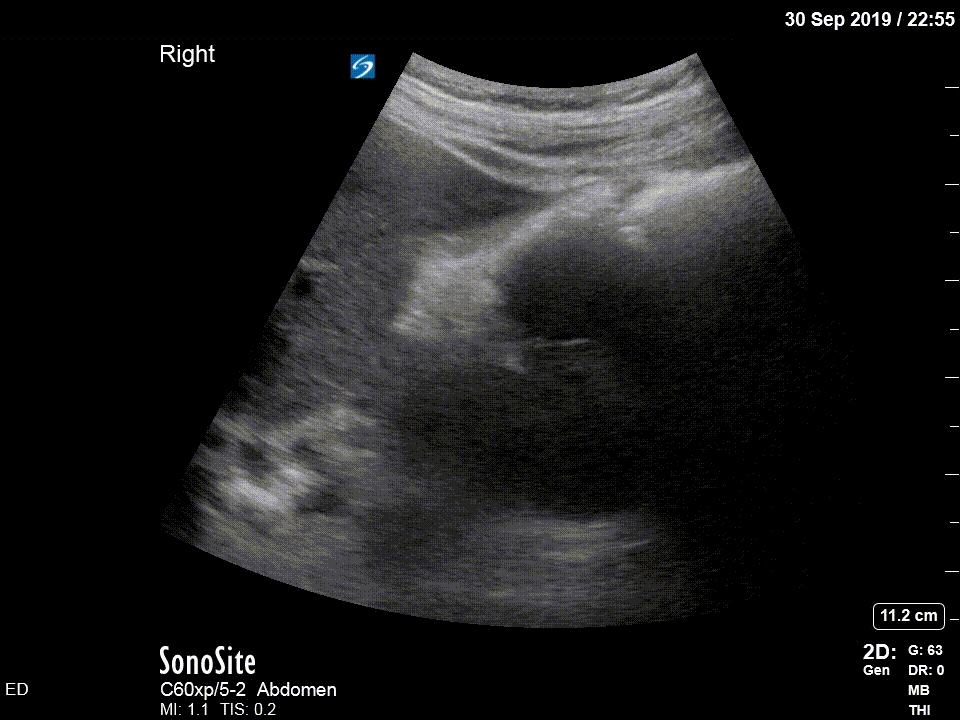

Bedside ultrasound was undertaken to assess for signs of ureteric obstruction.

There is moderate-to-severe hydronephrosis of the right kidney. There is mild hydronephrosis on the left. Colour flow doppler is used to demonstrate that the dilated pelvis and calyces are not normal blood vessels or aneurysms.

Hydronephrosis is dilation of the renal collecting system caused by increased pressure in the ureter, strongly suggesting downstream obstruction. Possible explanations for bilateral hydronephrosis include bladder outlet obstruction and bilateral ureteric obstruction. The former is unlikely in a freely urinating patient, especially female.